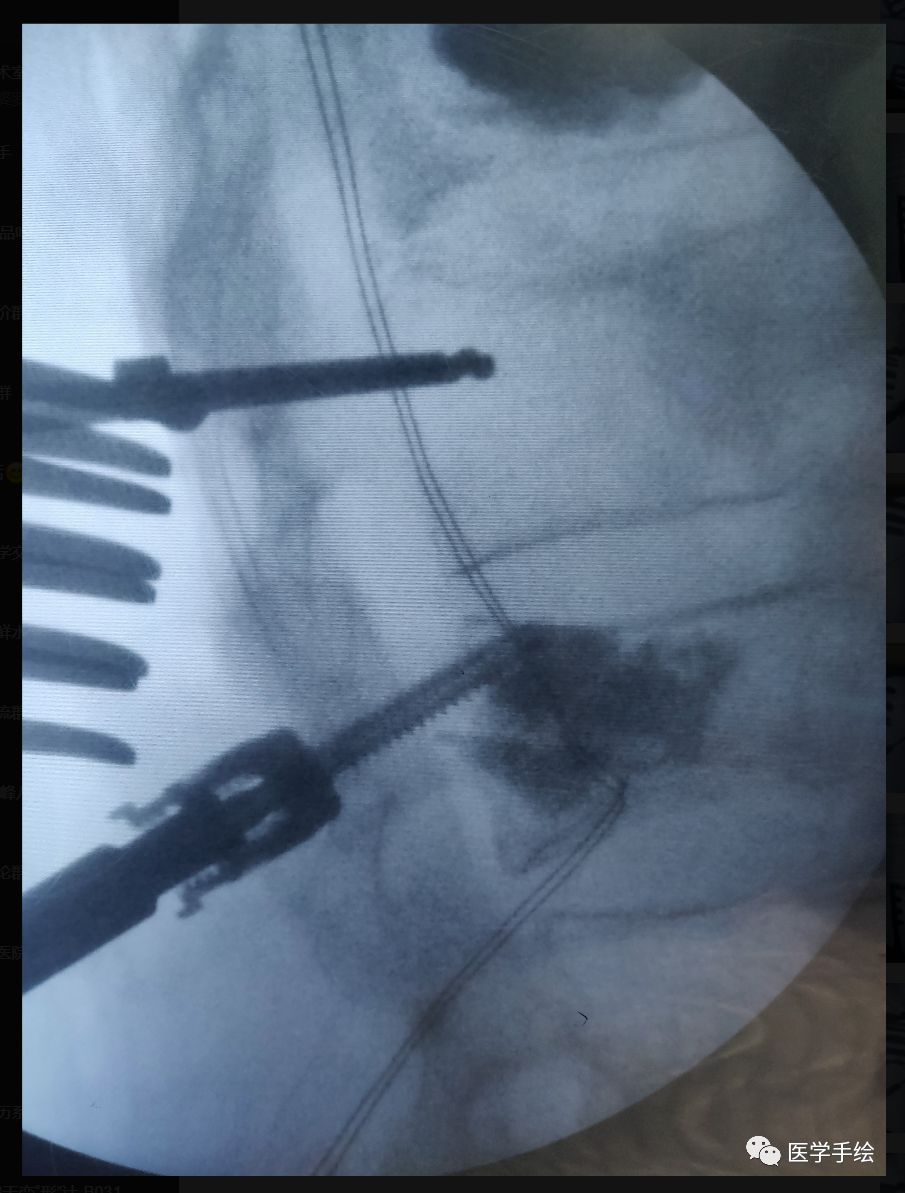

case:老年骨质疏松患者,既往L2行单侧(左侧)椎体成形手术。本次手术L2需要置入螺钉,左侧椎弓根螺钉由于骨水泥的存在置入困难,选择CBT螺钉。